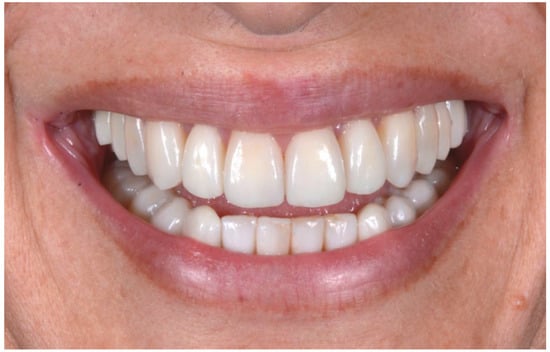

2.3. Outcome Achieved